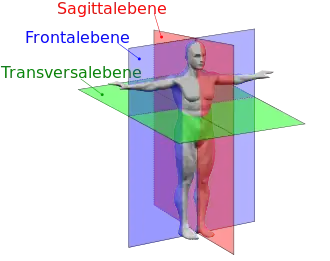

Die Sagittalebene durch die Körpermitte ist die Medianebene, sie teilt den Körper in eine rechte und eine linke Hälfte; in der nebenstehenden Abbildung wird diese spezielle Ebene als rote Fläche gezeigt. Ein Schnitt in dieser Ebene heißt Medianschnitt, in einer hierzu leicht versetzten Sagittalebene Paramedianschnitt. Eine Lage in der Medianebene heißt median, die Richtung dahin medial. Die Medianebene spielt auch als Bezugsebene außerhalb des Körpers eine Rolle, so etwa in der Akustik menschlichen Hörens (→ Blauertsche Bänder).